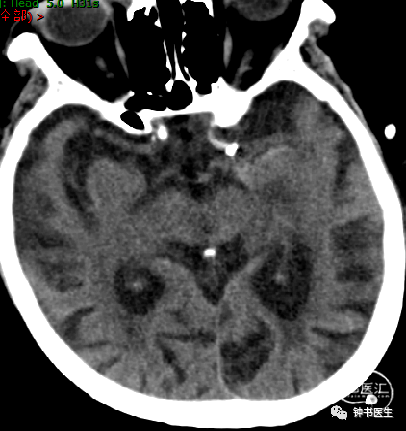

2019-1-16

神经重症治疗思路

血压:90-100mmHg

灌注压:60mmHg

脱水:三联

镇静镇痛(咪达唑仑+瑞芬)

ICP:10mmHg以内

2019-1-19